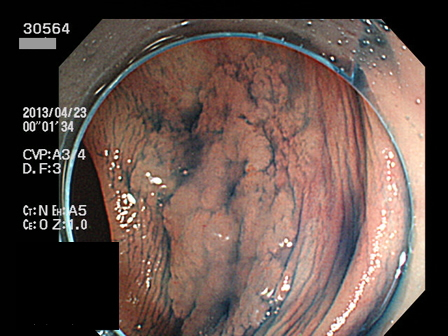

上の写真は「粘膜下層に微小浸潤したSSAP早期癌」で当院でEMRで根治し「ギリギリ・セーフ」でした。しかし、、いつも、このような「幸運」を期待していてはCMS4との闘いには勝てないでしょう。